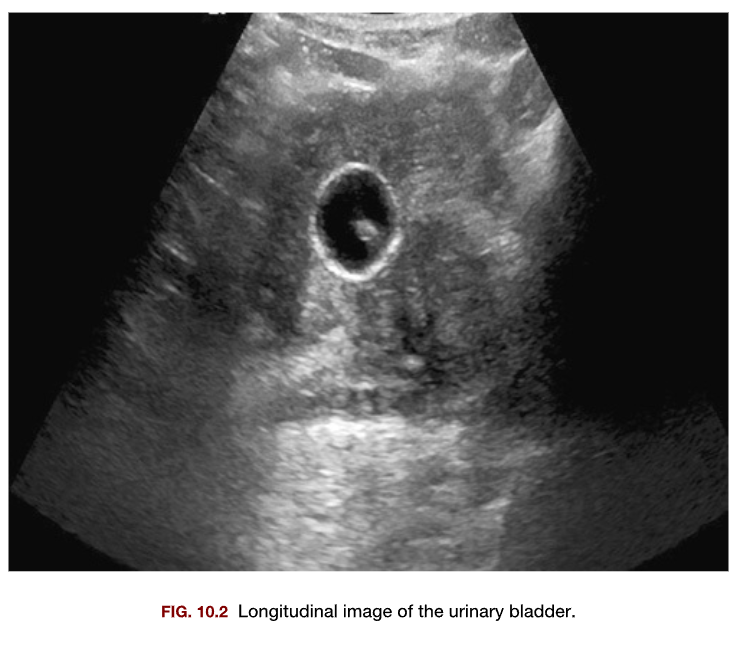

This sagittal image of the urinary bladder demonstrates a

1. Ureterocele

2. Bladder diverticulum

3. Catheter balloon

4. Small amount of residual urine

A

c. Catheter balloon